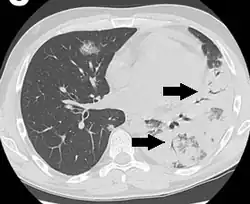

An air bronchogram is defined as a pattern of air-filled bronchi on a background of airless lung.[1]

In pulmonary consolidations and infiltrates, air bronchograms are most commonly caused by pneumonia or pulmonary edema (especially with alveolar edema).[2][3]

Other potential causes of consolidations or infiltrates with air bronchograms are:[2]